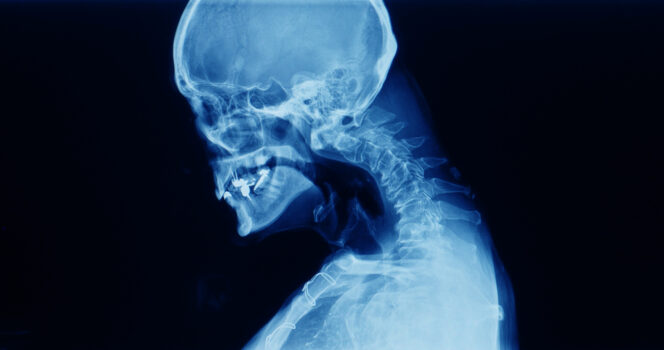

Een jonge man uit Iran bleek een alarmerende aandoening te hebben ontwikkeld. Zijn nek kon zijn hoofd niet meer dragen. Volgens de artsen was de man een amfetaminegebruiker. De stof, ook bekend als speed, zorgde ervoor dat zijn kin gedurende langere tijd op zijn borst viel, wat leidde tot een ‘vaste kyfotische nekpositie’.

Hij hield een extreme kromming in zijn nek over nadat hij regelmatig een groot aantal drugs had gebruikt, waaronder heroïne, opium en speed.

De CT-scan toonde aan dat zijn wervelkolom ernstig vervormd was. Volgens artsen leek de situatie te verbeteren toen hij onder algehele narcose was.